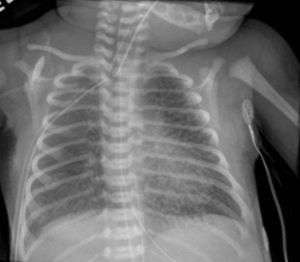

| Chest radiography showing severe pulmonary interstitial emphysema | |

Pulmonary interstitial emphysema (PIE) is a collection of air outside of the normal air space of the pulmonary alveoli, found instead inside the connective tissue of the peribronchovascular sheaths, interlobular septa, and visceral pleura. (This supportive tissue is called the pulmonary interstitium.) This collection of air develops as a result of alveolar and terminal bronchiolar rupture. Pulmonary interstitial emphysema is more frequent in premature infants who require mechanical ventilation for severe lung disease. Infants suffering from pulmonary interstitial emphysema are typically recommended for admission to a neonatal intensive care unit.